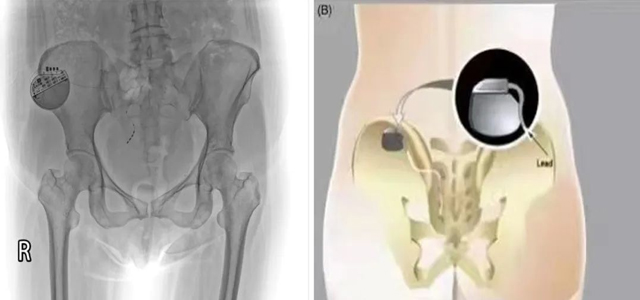

為緩解會(huì)陰及盆底疼痛給患者帶來(lái)的不適感,翟春寶主任及其團(tuán)隊(duì)經(jīng)科室討論后決定為該患者進(jìn)行骶神經(jīng)調(diào)控術(shù),并與患者及家屬耐心溝通。根據(jù)綜合評(píng)估,擇期局麻下行一期骶神經(jīng)調(diào)控器置入術(shù)。依據(jù)患者肛周感受調(diào)節(jié)控制器相關(guān)數(shù)值。

術(shù)后3月,患者自覺肛周墜脹明顯減輕(自述好轉(zhuǎn)70%以上),大小便控制能力較術(shù)前明顯改善。患者及家屬對(duì)一期調(diào)控效果非常滿意,完善相關(guān)檢查后行骶神經(jīng)調(diào)節(jié)器植入(二期)。

骶神經(jīng)調(diào)控:是指利用介入手段將一種短脈沖的刺激電流連續(xù)施加于特定的骶神經(jīng),以此剝奪神經(jīng)細(xì)胞本身的電生理特性、以便人為地激活興奮或抑制神經(jīng)通路、干擾異常的骶神經(jīng)反射弧,進(jìn)而影響由調(diào)節(jié)盆底等骶神經(jīng)支配的效應(yīng)器官的行為,起到“神經(jīng)調(diào)控”的作用。

骶神經(jīng)調(diào)控 (SacralNeuromodulation, SNM)作為醫(yī)學(xué)科學(xué)、疾病治療的新興科學(xué),是當(dāng)代醫(yī)學(xué)研究和臨床實(shí)踐的熱點(diǎn),是當(dāng)今解決功能障礙性疾病的必需手段。